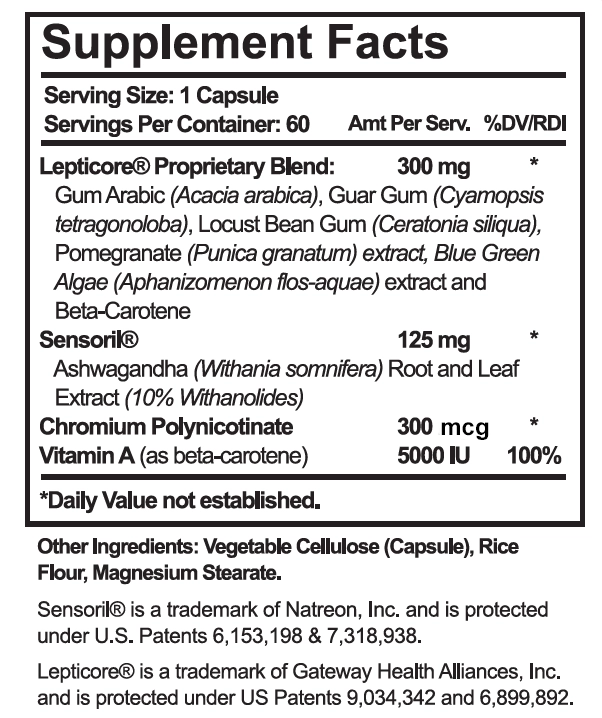

What Ingredients are in LeptiSense?

You’ll be able to find a less expensive form of “Indian Ginseng” found in Sensoril… but you simply cannot find a higher quality, certified potent, certified pure form found in Sensoril.

And as for Lepticore with its PEA and mix of high quality, plant-based micronutrients and antioxidants? It’s only available as the proprietary, quality-ensured combination found in Leptisense.